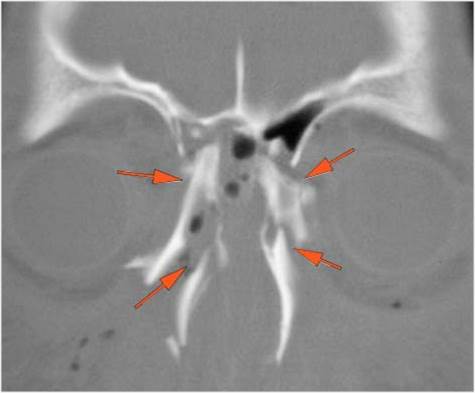

Possible facial, mandibular, orbital, and/or skull fractures, due to craniofacial trauma.Exam

Non-contrast CT of the maxillofacial region was obtained with 0.5-1.0 mm thick sections in the axial plane and reformatted 3D and/or in the coronal and sagittal planes and viewed interactively in 3 dimensions at the computer workstation.